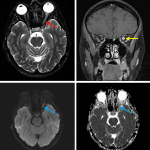

- Enlarged intraorbital left optic nerve with T2/STIR hyperintensity, restricted diffusion, and marked enhancement

- Optic neuritis

Findings consistent with left optic neuritis.